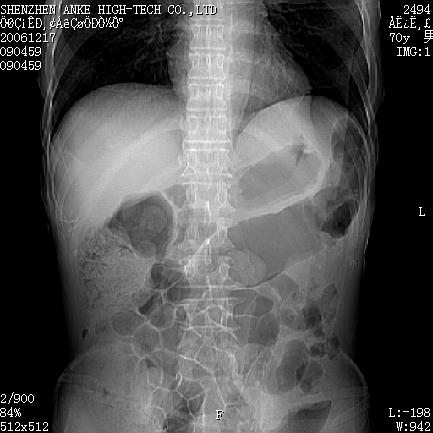

患者:男,70岁,腹部疼痛待查.b超见左肾脏占位待排.因为患者经济条件不好,没有做增强.

支持胰腺癌伴肝转移;左肾囊肿?

胰尾与左肾上缘部位见有一肿块影,密度不均匀,周围边界不清晰,与胰腺相连,与左肾边界不清,肝脏内见有多发低密度影,考虑胰尾癌伴左肾侵犯并肝内转移。最好是做个增强。

考虑:1,胰腺癌伴肝转移;2,左肾小囊肿。

与胃、脾及左肾之间见一巨大肿块影,其内密度不均,边界欠清,与胰腺关系密切。肝实质内见多个类圆形低密度灶,边界较清。符合胰腺癌并肝转移表现。

考虑:1,胰腺癌伴肝转移;2,左肾小囊肿. 3胰腺病变与左肾分界不清,肾脏可能受累。

与胃、脾及左肾之间见一巨大肿块影,其内密度不均,边界欠清,与胰腺关系密切。肝实质内见多个类圆形低密度灶,边界较清。符合胰腺癌并肝转移表现。

同意胰尾部癌累及左肾前,肝多发转移,左肾小囊肿。

胰尾与左肾上缘部位见有一肿块影,密度不均匀,周围边界不清晰,与胰腺相连,与左肾边界不清,肝脏内见有多发低密度影,考虑胰尾癌伴左肾侵犯并肝内转移。最好是做个增强。